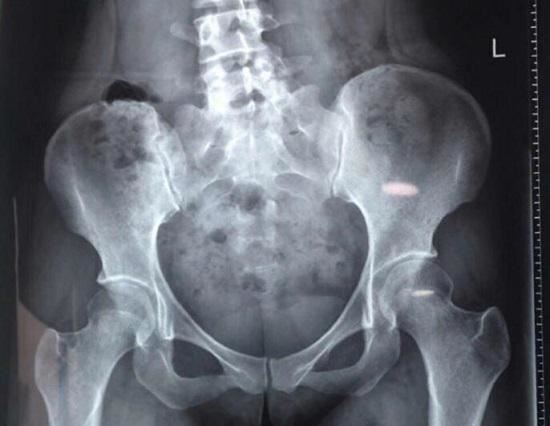

所谓腰,主要是指下腰背,也就是腰椎和骶骨(骶骨就是屁股住上的那块宽大的骨𧂙�、)的位置。显而易见,孩子也有腰,河北保定252医院之所以说孩子没腰,主要有两层含义:1、文化传承的结果,腰的发音同“夭”,古时候医疗条件差,孩子夭折的概率极高,说孩子有“夭”显然不是什么吉利话,流传下来的结果就是“孩子没有腰”;2、腰椎病主要是一种退行性变(老化)的结果,孩子很少会患上腰赵迎椎病。

5、隐性脊柱裂、漂浮棘突、椎体畸形等问题都可能会引发腰痛。如果孩子的疼痛是𐨵𐙍长期的、慢性的,或者存在脊柱畸形(例如:脊柱侧弯、长短腿、高低肩等),应该去医院进行排查。6、生理性疼痛。例如,小�、女生出现月经时也会“腰痛”,孩子不太会区分腰痛与腹痛的不同򦘯之处(有时确实会很像),会笼统地描述为腰痛。

腰椎侧凸、骨盆高度不一